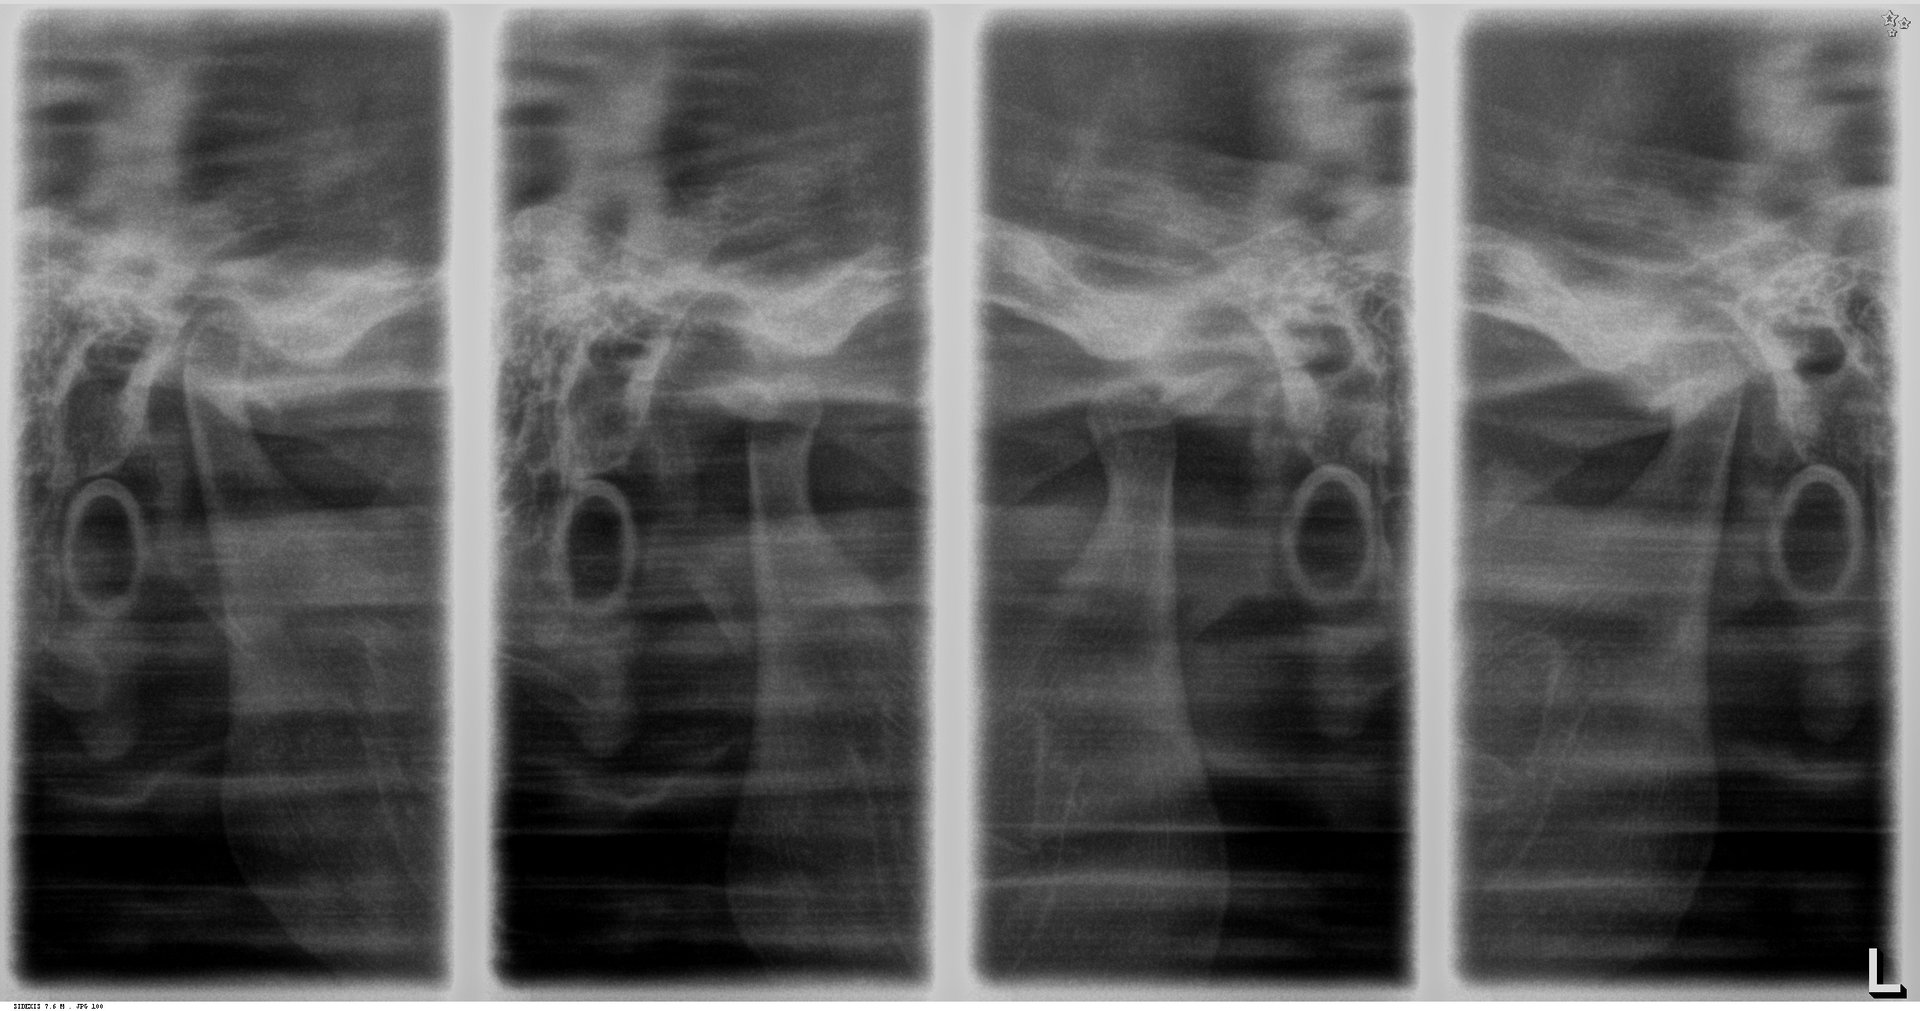

Radiografía de ATM Comparativa

Una evaluación detallada es esencial para abordar los trastornos temporomandibulares (ATM) con eficacia. La radiografía de ATM comparativa es tu herramienta de elección para obtener una visión precisa de las articulaciones temporomandibulares de ambos lados, permitiéndote comparar y analizar las condiciones de manera detallada.